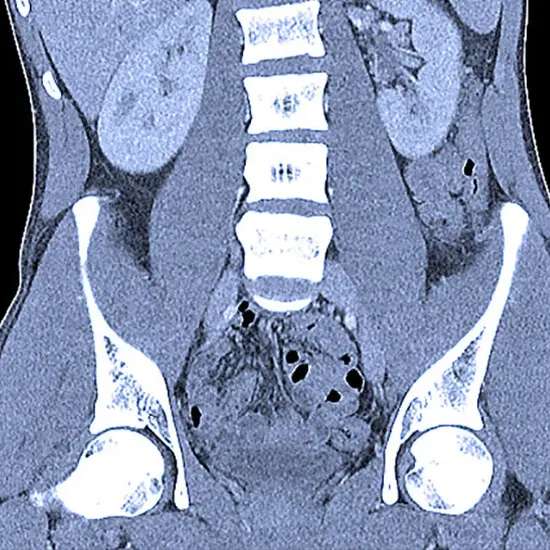

Typically, a PET CT scan generates a giant wide variety of snapshots that want to be reviewed cautiously to become aware of any abnormalities. The pix are normally reviewed through a radiologist or a nuclear medicinal drug doctor who has specialized coaching in deciphering PET CT scans. The procedure of reviewing the photos includes assessing the metabolic endeavor of unique tissues and organs in the physique and evaluating them to the everyday variety of activity.